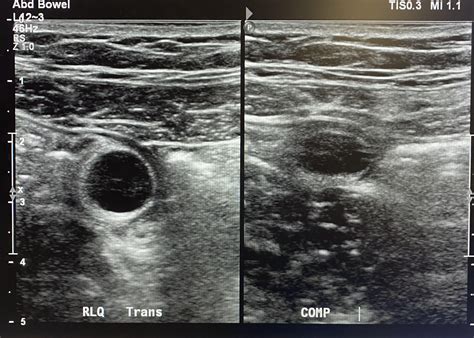

When performing an ultrasound to diagnose appendicitis, radiologists look for several key signs:

• Appendiceal Diameter: A normal appendix is typically less than 6 mm in diameter. An inflamed appendix will often be larger than 6 mm.

• Appendiceal Wall Thickness: The wall of the inflamed appendix may appear thicker than normal.

• Appendicoliths: These are small, calcified stones that can be seen within the appendix on ultrasound. Their presence can indicate a higher risk of appendicitis.

• Hyperemia: Increased blood flow to the appendix, which can be detected using Doppler ultrasound, is another sign of inflammation.

• Periappendiceal Fluid: The presence of fluid around the appendix can indicate inflammation or infection.

• Probe Placement: The ultrasound probe is placed on the right lower quadrant of the abdomen, where the appendix is located.

• Image Acquisition: The radiologist moves the probe to capture images of the appendix from different angles. Doppler ultrasound may be used to assess blood flow.

• Interpretation: The images are reviewed to look for the signs of appendicitis mentioned earlier.